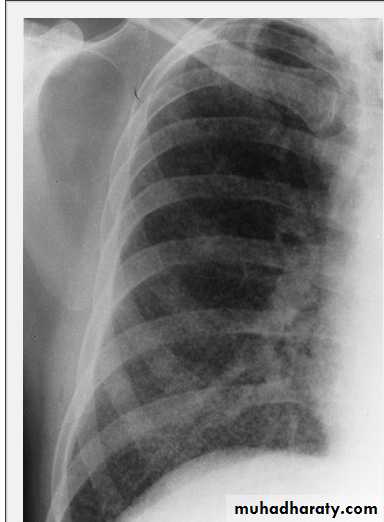

Tension pneumothorax.

On a posteroanterior chest x-ray (A), the left hemithorax is very dark or lucent because the left lung has collapsed completely (white arrows).

The tension pneumothorax can be identified because the mediastinal contents, including the heart, are shifted toward the right, and the left hemidiaphragm is flattened and depressed. A computed tomography scan done on a different patient with a tension pneumothorax (B) shows a completely collapsed right lung (arrows) and shift of the mediastinal contents to the left.

Tension Pneumothorax. Portable chest film in a 43-year-old woman with ARDS shows a large right pneumothorax with mediastinal shift and ipsilateral diaphragmatic depression, suggesting tension.

Air was evacuated under pressure during emergent placement of a right chest tube.